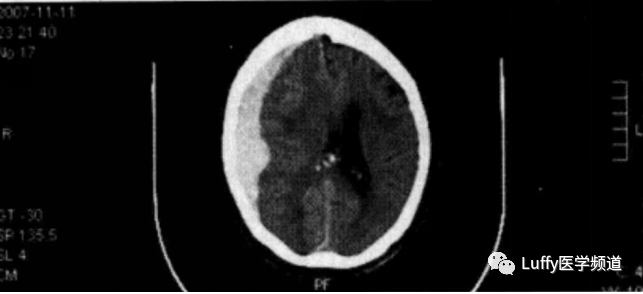

体格检查发现该患者主要为躯体阳性体征和左侧第V脑神经麻痹。后颈部触痛,双肺听诊呈清音,腹部膨隆,有反跳痛,肠鸣音消失。在车祸现场和急诊室输注3L的生理盐水后,实验室检查结果如下:Hb 96g/L,WBC 13×109/L,Na+ 145mmol/L,K+ 3.6mmol/L,HCO3- 18mmol/L,Cl - 110mmol/L,肌酐1.4mg/dl,BUN 31mg/ dl。腹腔穿刺可抽出血性液体。胸部X线片提示膈下游离气体。头颅和颈部CT提示双侧额叶挫伤和右侧额顶叶一中等大小的硬膜下血肿(图13.1)。腹部CT提示盲肠穿孔。

图13.1右侧额顶骨硬膜下血肿伴脑室受压及颅内压增加证据